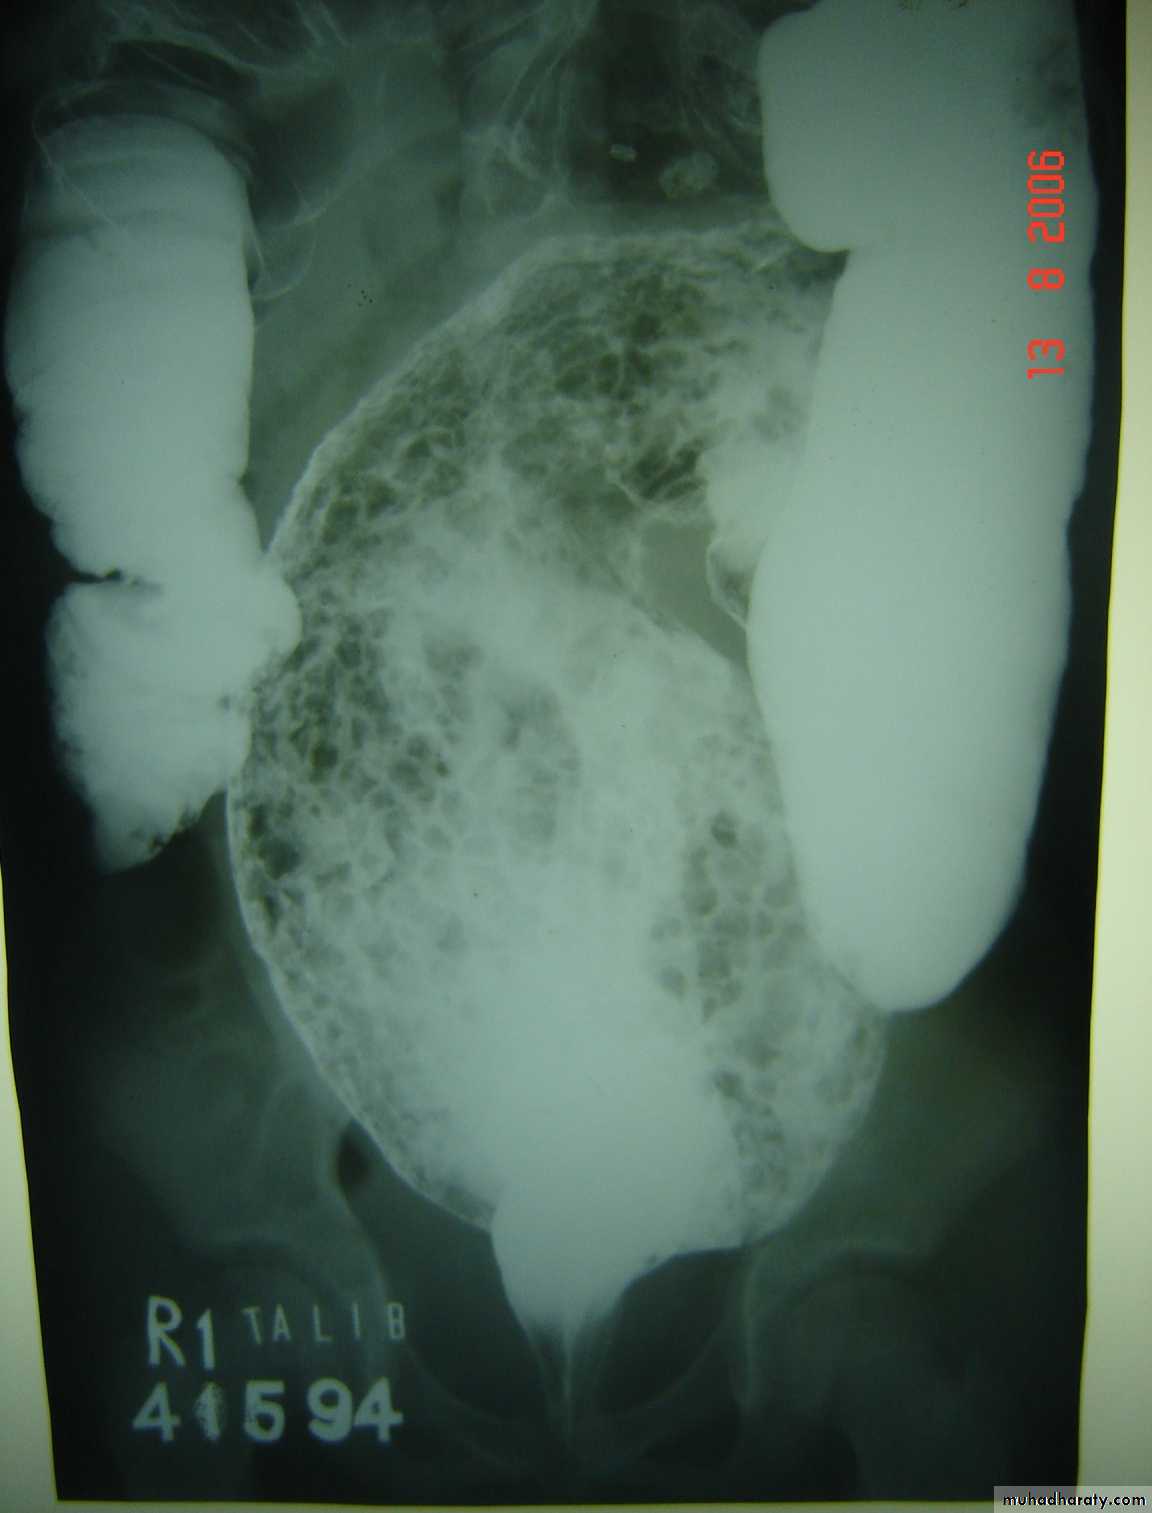

Hirschprungs disease